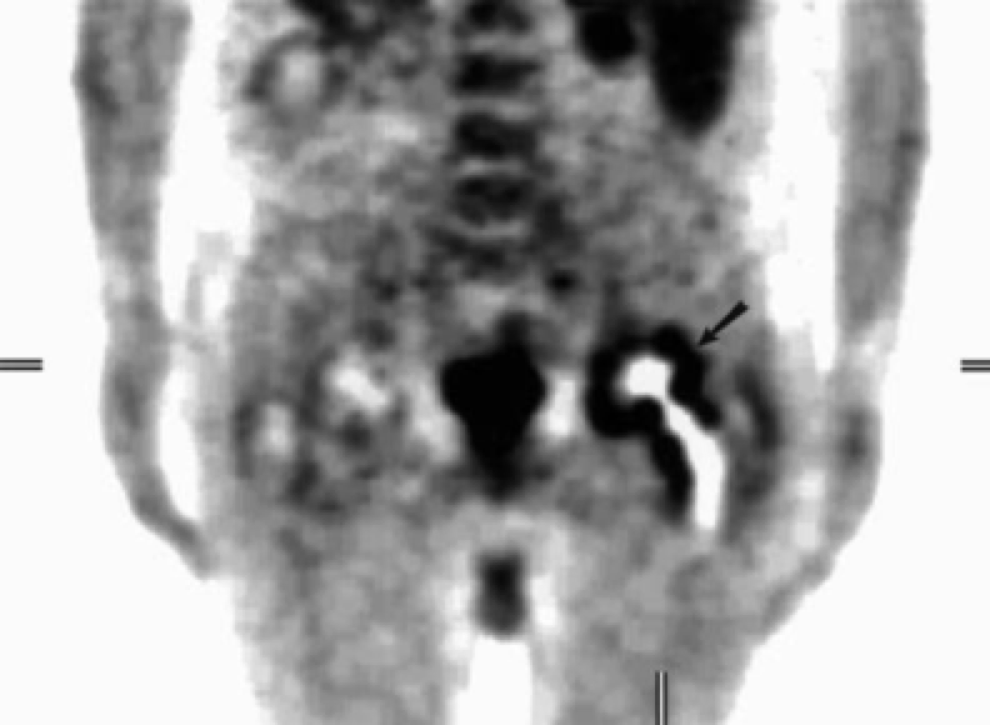

5. Metal-on-metal(MOM)disease:

假性滑囊,是金属对金属髋关节置换的组织反应;表现为髋关节假体周围的滑囊。最常见的部位是:髋臼上缘、大粗隆和小粗隆。

人工髋关节置换术。假体周围囊性肿块(箭头)